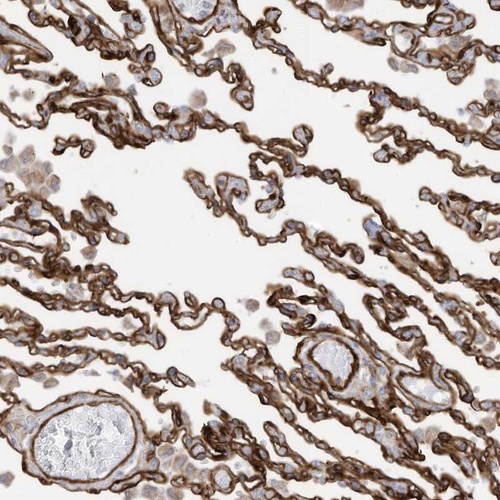

Immunohistochemical staining of human lung shows strong membranous positivity in alveolar cells.